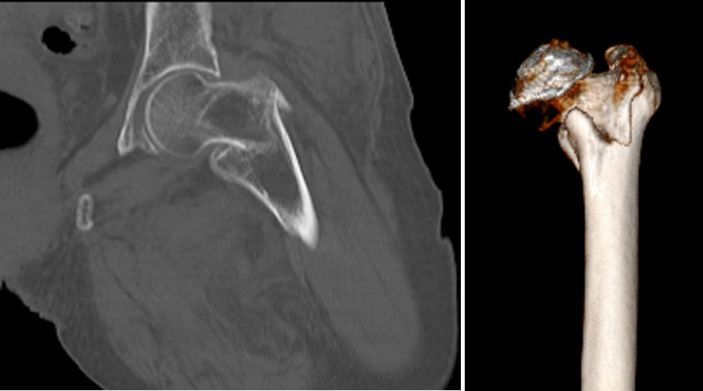

吳志斌主任通過CT+三維重建先行拟定詳細手術方案,提前做了精心準備。根據患者的年齡特征,爲其選擇最佳的半髋置換方案,并采用雙動人工股骨頭,提高活動範圍,減少髋臼磨損。